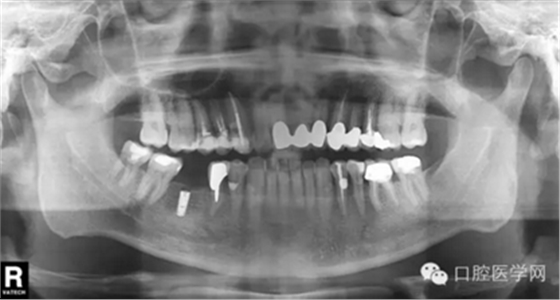

第二种种植体是 NobelReplace系统

X光片显示为: